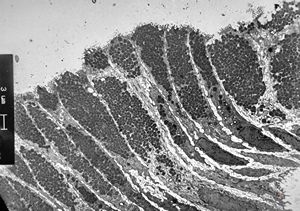

normal mucosa - stomach